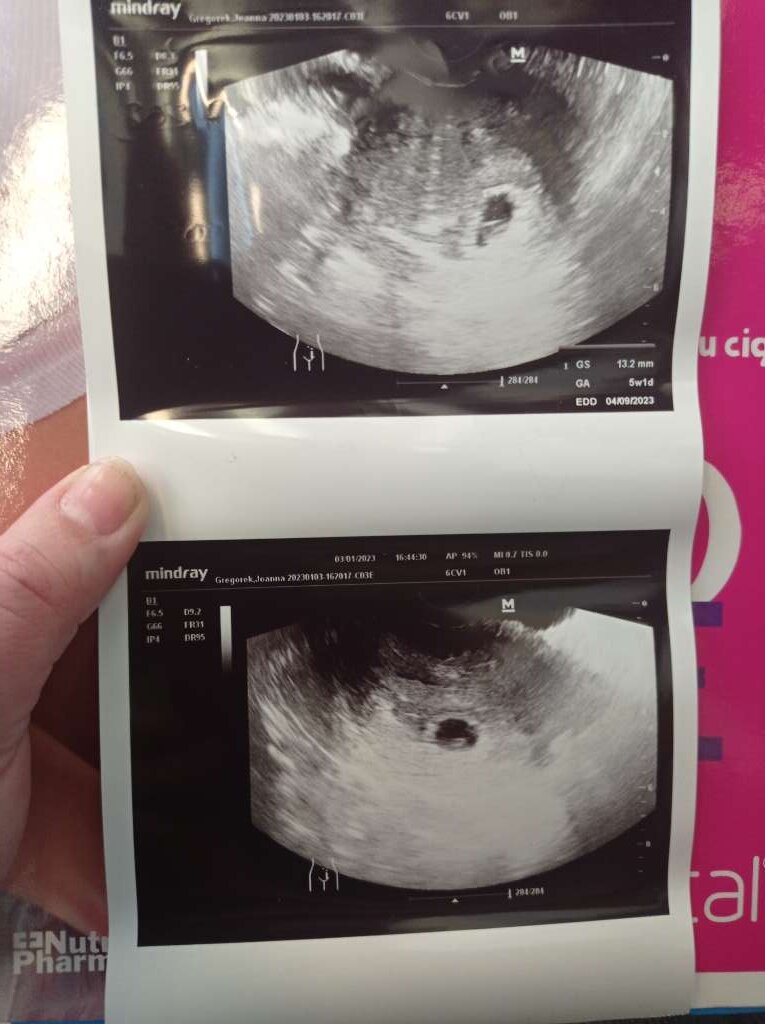

Byłam na USG jest zarodek z akacją serca, ale co z tego jak wychodzi 5+5 a ja jestem już 7+4 i nawet lekarka kręciła nosem że coś nie tak, dodatkowo pęcherzyk żółtkowy ma średnicę 7mm a powinien max 6 i to też źle wróży o wadach genetycznych. Jak znowu będę musiała to przeżywać to się załamię. Jak ta ciąża będzie się rozwijać to napewno robię amniopunkcję w 15 tc